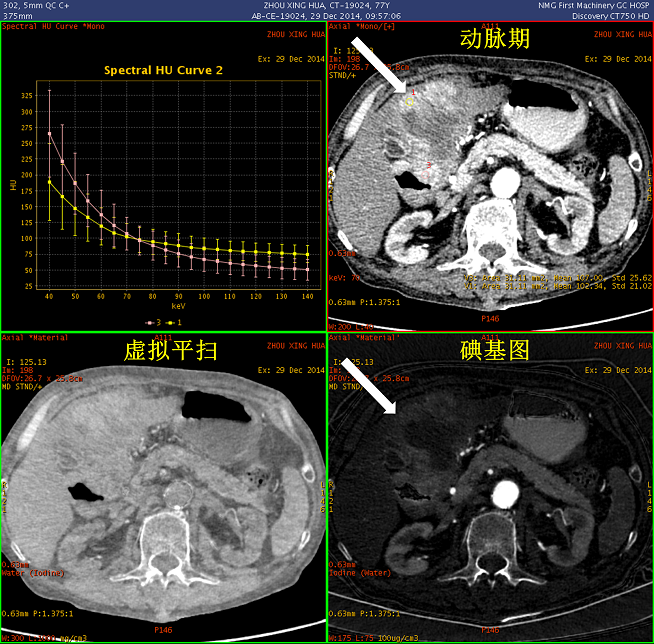

观察不同期相显示:胃窦部及十二指肠区团块,碘基图呈高密度证明有强化(白箭); 胃及十二指肠壁呈明显增厚,范围较广,胃及肠腔明显狭窄(碘基图尤为明显); 肝左叶受压明显

病灶内部密度不均,最大径线:7 × 11cm; GSI曲线分析:增厚的胃壁与外凸的部分能谱曲线一致,证明巨大病灶起源于胃; 延迟期观察,对比剂通过未受明显影响,胃壁无明显僵硬

实质期能谱曲线分析,显示病灶与腹腔内正常淋巴结曲线已有区别

三维融合图像清晰显示病灶轮廓:肝动静脉呈“抱球征”,提示横断位图像所见的肝左叶区域的病灶并非肝实质内,而为受压及部分容积效应所致